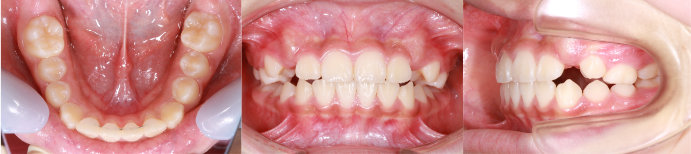

| Case2 |

| 出っ歯 |

| <治療前> |

| <治療後> |

| 主訴 |

上の前歯が出ている |

| 診断名 |

上顎前突 |

| 年齢 |

8歳 |

| 使用装置 |

マルチブラケット装置/ヘッドギア |

| 抜歯部位 |

永久歯の抜歯は無し |

| 治療期間 |

3年6か月 |

| 治療費概算 |

検査・診断料:5万円+税 装置・技術料:25万円+税 来院ごとの処置・管理料:5,000円+税 保定装置料:5万円+税 |

| リスク・副作用 |

特になし |